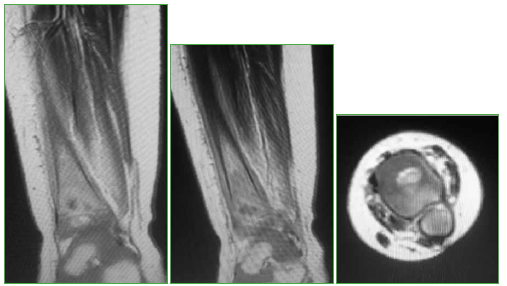

Tibia osteomyelitis secondary to BCG vaccination in an immunocompetent infant. Case report

Introduction: The Bacillus Calmette-Guérin (BCG) vaccine, used to prevent severe forms of tuberculosis (TB), is the most extensively used vaccine worldwide. Adverse events associated with BCG vaccination are rare, and most of them occur at the inoculation site. We present a tibia Osteomyelitis case secondary to BCG vaccination in an immunocompetent infant.

Conclusions: Bone involvement secondary to BCG vaccination in previously healthy patients is extremely rare. Healthcare providers must consider such settings in order to make the diagnosis and institute the appropriate treatment. Antituberculous drugs produced good therapeutic results with no need for surgical toilette.